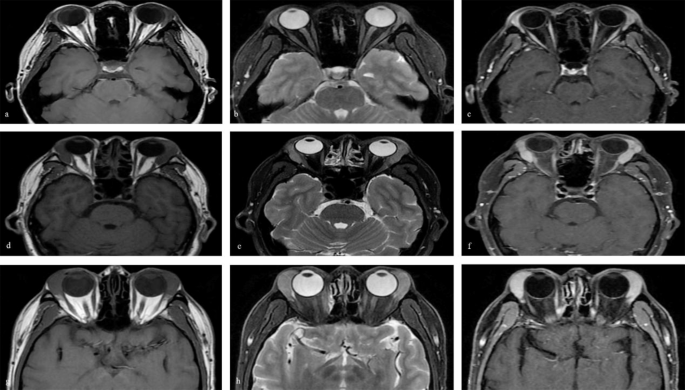

Imaging scans were conducted on 511 patients (87.8%), revealing lacrimal gland enlargement in all cases; 127(21.8%) of these patients exhibited enlargement in both lacrimal glands. Patients with inflammatory lacrimal gland lesions typically presented with diffuse enlargement while retaining an almond-shaped gland, as seen in conditions like dacryoadenitis (Fig. 2a-c). Lymphoproliferative lesions and epithelial tumors, such as IgG4-ROD (Fig. 2d-f) and MALT lymphoma (Fig. 2g-i), were generally.

characterized by a scallop-like mass occupying the lacrimal gland. Dacryops was predominantly identified by its cystoid mass presentation.

a, d, and g: Bilateral lacrimal glands enlargement with moderate signal on MRI T1-weighted images (horizontal view). b, e, h: Bilateral lacrimal glands enlargement with slightly higher signal on MRI T2-weighted images (horizontal view). c, f, and i: B Bilateral lacrimal glands enlargement with high signal on fat-suppressed T1-weighted enhanced MRI scans (horizontal view).

MRI magnetic resonance imaging, IgG4-ROD Immunoglobulin G4-related ophthalmic disease, MALT Mucosa associated lymphoid tissue.